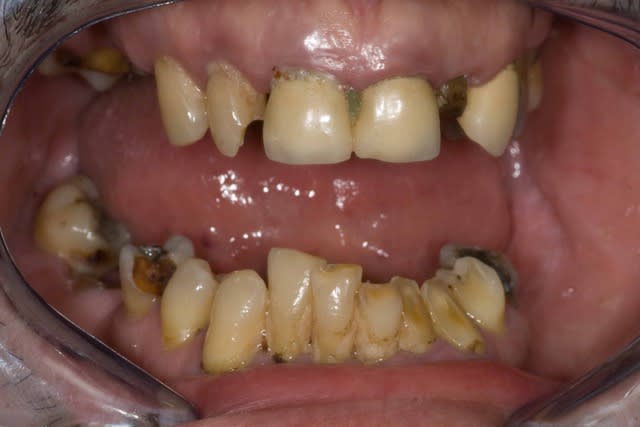

Patient vu vendredi passé...

Endo 21-11-12-13

Il reste aussi 15 et 26

Plan de tx :

Pas d'implants...pour l'instant

Couronnes 12, 11 et 26

Bridges 15-X-13 et 21-X-23

Stellite

Alors, IC ou pas sur les endo ?

13 ?

12 ?

11 ?

21 ?

Pour le bas...vendredi prochain...à suivre

Bonnes racines, pas de mobilité

Le sujet n'est pas la séquence, ni le plan de tx, mais savoir quelles dents IC ou bien tenons fibrés + résine...

C'est pas un cas d'école, super bien préparé,trop parfait, avec devis de 30,000€, mais un cas assez banal, d'un patient ordinaire (plusieurs pensent que mes patients sont tous hyper soigneux de leurs dents...pffft....)

1) Patient qui semble bruxoman

2) Perte du calage postérieur donc propulsion de la mandibule pour rechercher de la proprioception avec les dents antérieures ( bonne change pour le remettre en relation centrée !).

3) Augmentation de DV ou elongation coronaire semble nécéssaire

4) Vu le parodonte du Patient et le sexe masculin .Il doit avoir des masseters comme des biceps

5) Le patient ne semble pas avoir une exigence esthétique enorme

6) Tu vas faire des stellites avec attachements qui vont encore plus augmenter la tension sur les cérams.

Si tu cherches les limites mécaniques des reconstitutions fibrées , crois moi tu vas dans le mur direct. Si tu poses la question juste pour faire polémique sache que c'est débile car face a un cas comme ca meme ma grand mere poserait des IC.